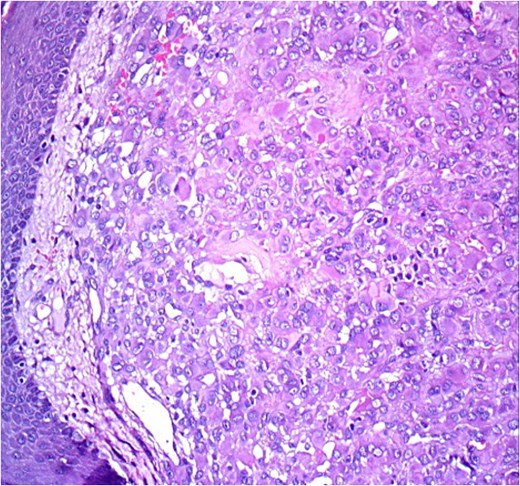

Histopathological analysis revealed a poorly differentiated dermal neoplasm arranged in a solid growth pattern. The tumor cells were epithelioid, with abundant eosinophilic cytoplasm and centrally or eccentrically placed nuclei exhibiting moderate atypia and prominent nucleoli (Figs 1 and 2). The mitotic rate was 4 per 10 high-power fields (HPF). The stroma was fibrous, and the surgical margins were involved. Immunohistochemical analysis showed tumor cells positive for vimentin, CK7, and S100 protein, with a MIB-1 proliferation index of 5%. Negative staining for cytokeratin, androgen receptors, PHLDA1, and p63 excluded adnexal tumors. Additionally, vascular markers (CD34, CD31, ERG), muscular markers (desmin, caldesmon, actin, myogenin), histiocytic markers (CD68, CD163, MMP11), plasmacytic markers (CD138, MUM1), and melanocytic markers (Melan-A, HMB45) were negative.

HE ×20: A diffuse poorly differentiated neoplasm composed of pleomorphic epithelioid cells.